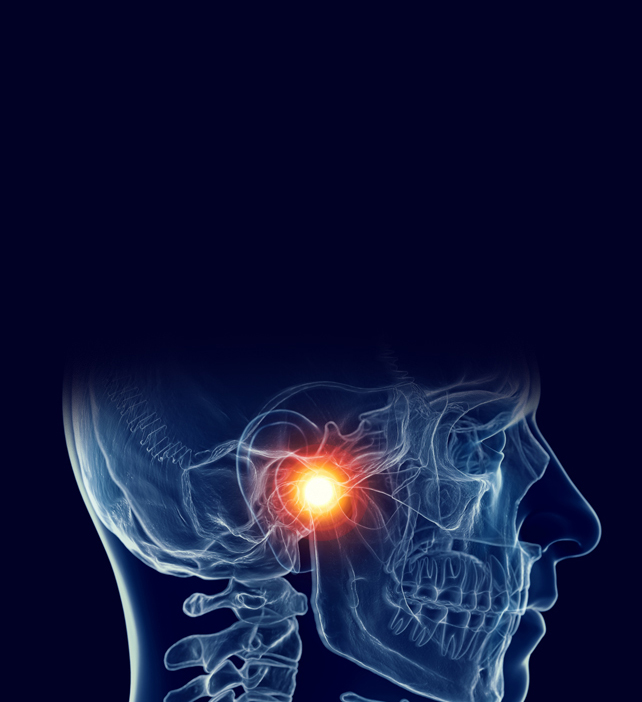

턱관절 치료

• 턱관절 치료

• 물리치료

보톡스치료

약물치료

스플린트